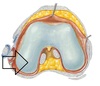

PCL

Attachment of ACL